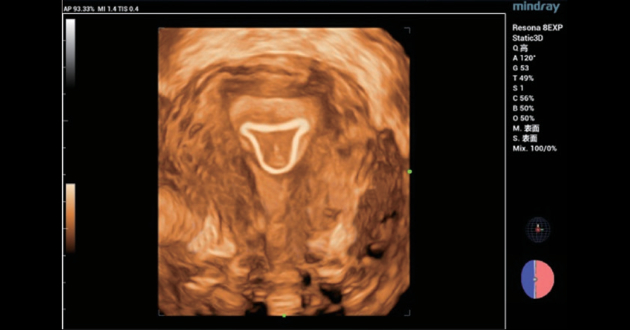

?? 2 ???? IUD ??

? ? ? ?? ???? IUD ?? ??? ?? 34? ??? ??? ???? ?? ?? ???????. 2D?????? IUD? ?? ??? ????, 3D ????? IUD? ??? ??? ??? ?? ??? ??? ??? ?????(?? 3, ?? 4). ???? 3D ???? ???? ??? ??? ???? ?? IUD? ?? ??? IUD? ???????.